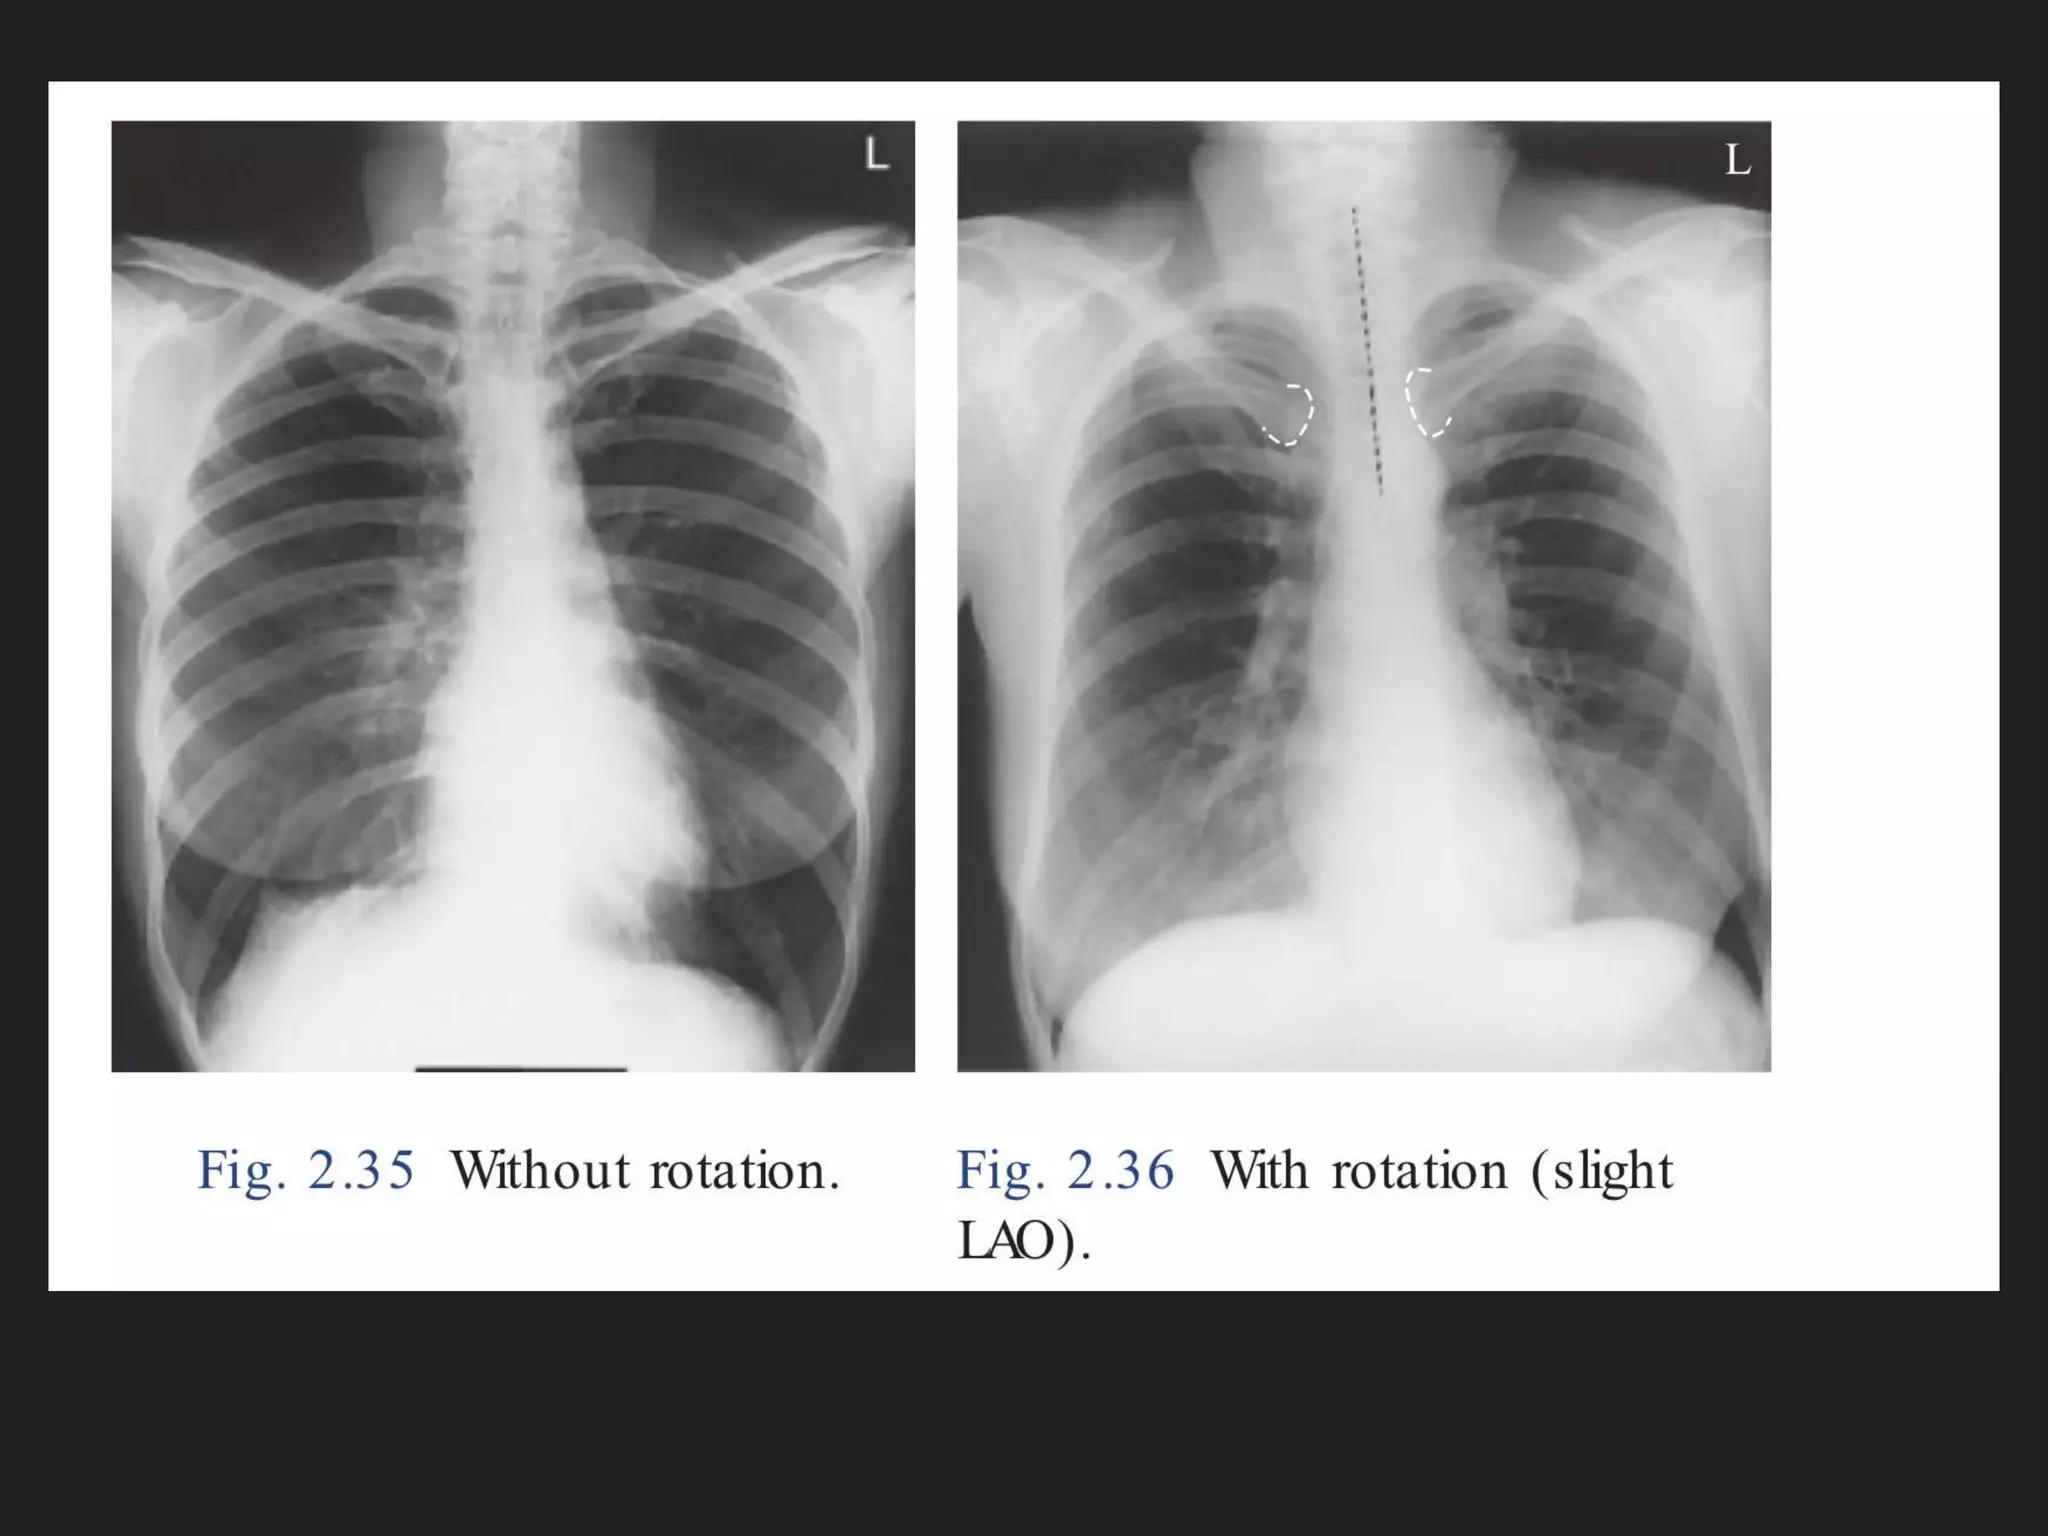

The document provides detailed instructions for performing a chest x-ray, emphasizing proper patient positioning and technical requirements for optimal image quality. Key points include centering the trachea, ensuring full inspiration, and visibility of specific anatomical features. Additionally, it outlines collimation margins and patient stance to achieve a clear view of lung fields.